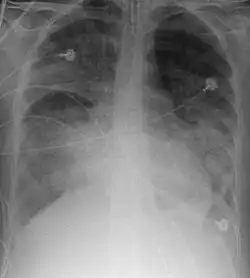

X-ray

Chest X-ray is the most common method used for diagnosis,[42] and may be used to confirm a diagnosis already made using clinical signs.[23] Consolidated areas appear white on an X-ray film.[47] Contusion is not typically restricted by the anatomical boundaries of the lobes or segments of the lung.[31][48][49] The X-ray appearance of pulmonary contusion is similar to that of aspiration,[36] and the presence of hemothorax or pneumothorax may obscure the contusion on a radiograph.[29] Signs of contusion that progress after 48 hours post-injury are likely to be actually due to aspiration, pneumonia, or ARDS.[13]

Although chest radiography is an important part of the diagnosis, it is often not sensitive enough to detect the condition early after the injury.[40] In a third of cases, pulmonary contusion is not visible on the first chest radiograph performed.[10] It takes an average of six hours for the characteristic white regions to show up on a chest X-ray, and the contusion may not become apparent for 48 hours.[10][31][48] When a pulmonary contusion is apparent in an X-ray, it suggests that the trauma to the chest was severe and that a CT scan might reveal other injuries that were missed with X-ray.[2]